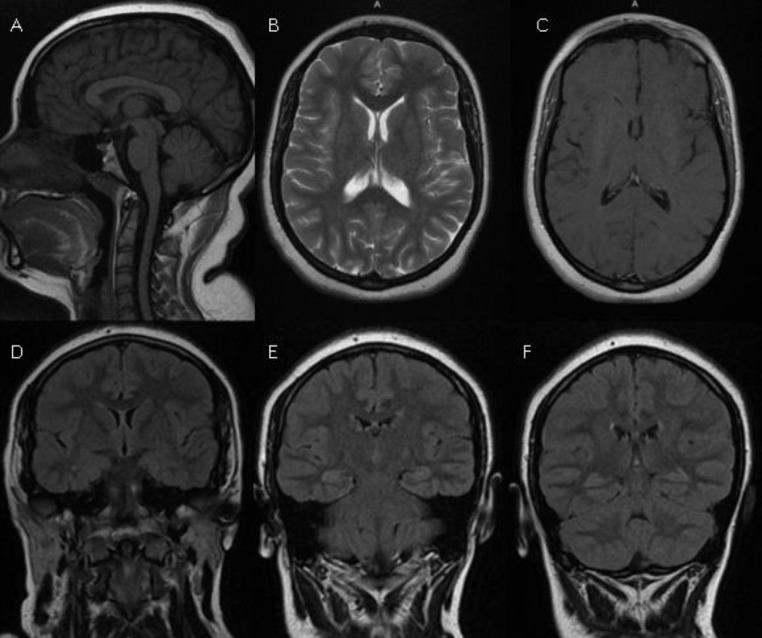

We described in this article a 19-year-old girl with an intracranial hypertension as an initial presentation of neuropsychiatric lupus. The brain MRI showed diffuse, bilateral and symmetrical white and grey matter hyperintensities. These lesions completely disappeared after 3 months of treatment. Diffuse cerebral edema with or without leukoencephalopathy in neuropsychiatric systemic lupus erythematosus is an extremely rare entity.

我们在本文中描述了一名19岁女孩,其以颅内高压作为神经精神性狼疮的初始表现。脑部磁共振成像显示弥漫性、双侧对称的白质和灰质高信号。经过3个月的治疗,这些病变完全消失。神经精神性系统性红斑狼疮中伴有或不伴有白质脑病的弥漫性脑水肿是一种极其罕见的情况。